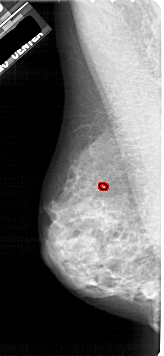

A_1914_1.RIGHT_CC

RIGHT_CC LINES 5041 PIXELS_PER_LINE 2446 BITS_PER_PIXEL 12 RESOLUTION 43.5 NON_OVERLAY

FILE: A_1914_1.LEFT_CC.OVERLAY

TOTAL_ABNORMALITIES 1

ABNORMALITY 1

LESION_TYPE CALCIFICATION TYPE PLEOMORPHIC DISTRIBUTION CLUSTERED

ASSESSMENT 4

SUBTLETY 2

PATHOLOGY BENIGN

TOTAL_OUTLINES 1

BOUNDARY